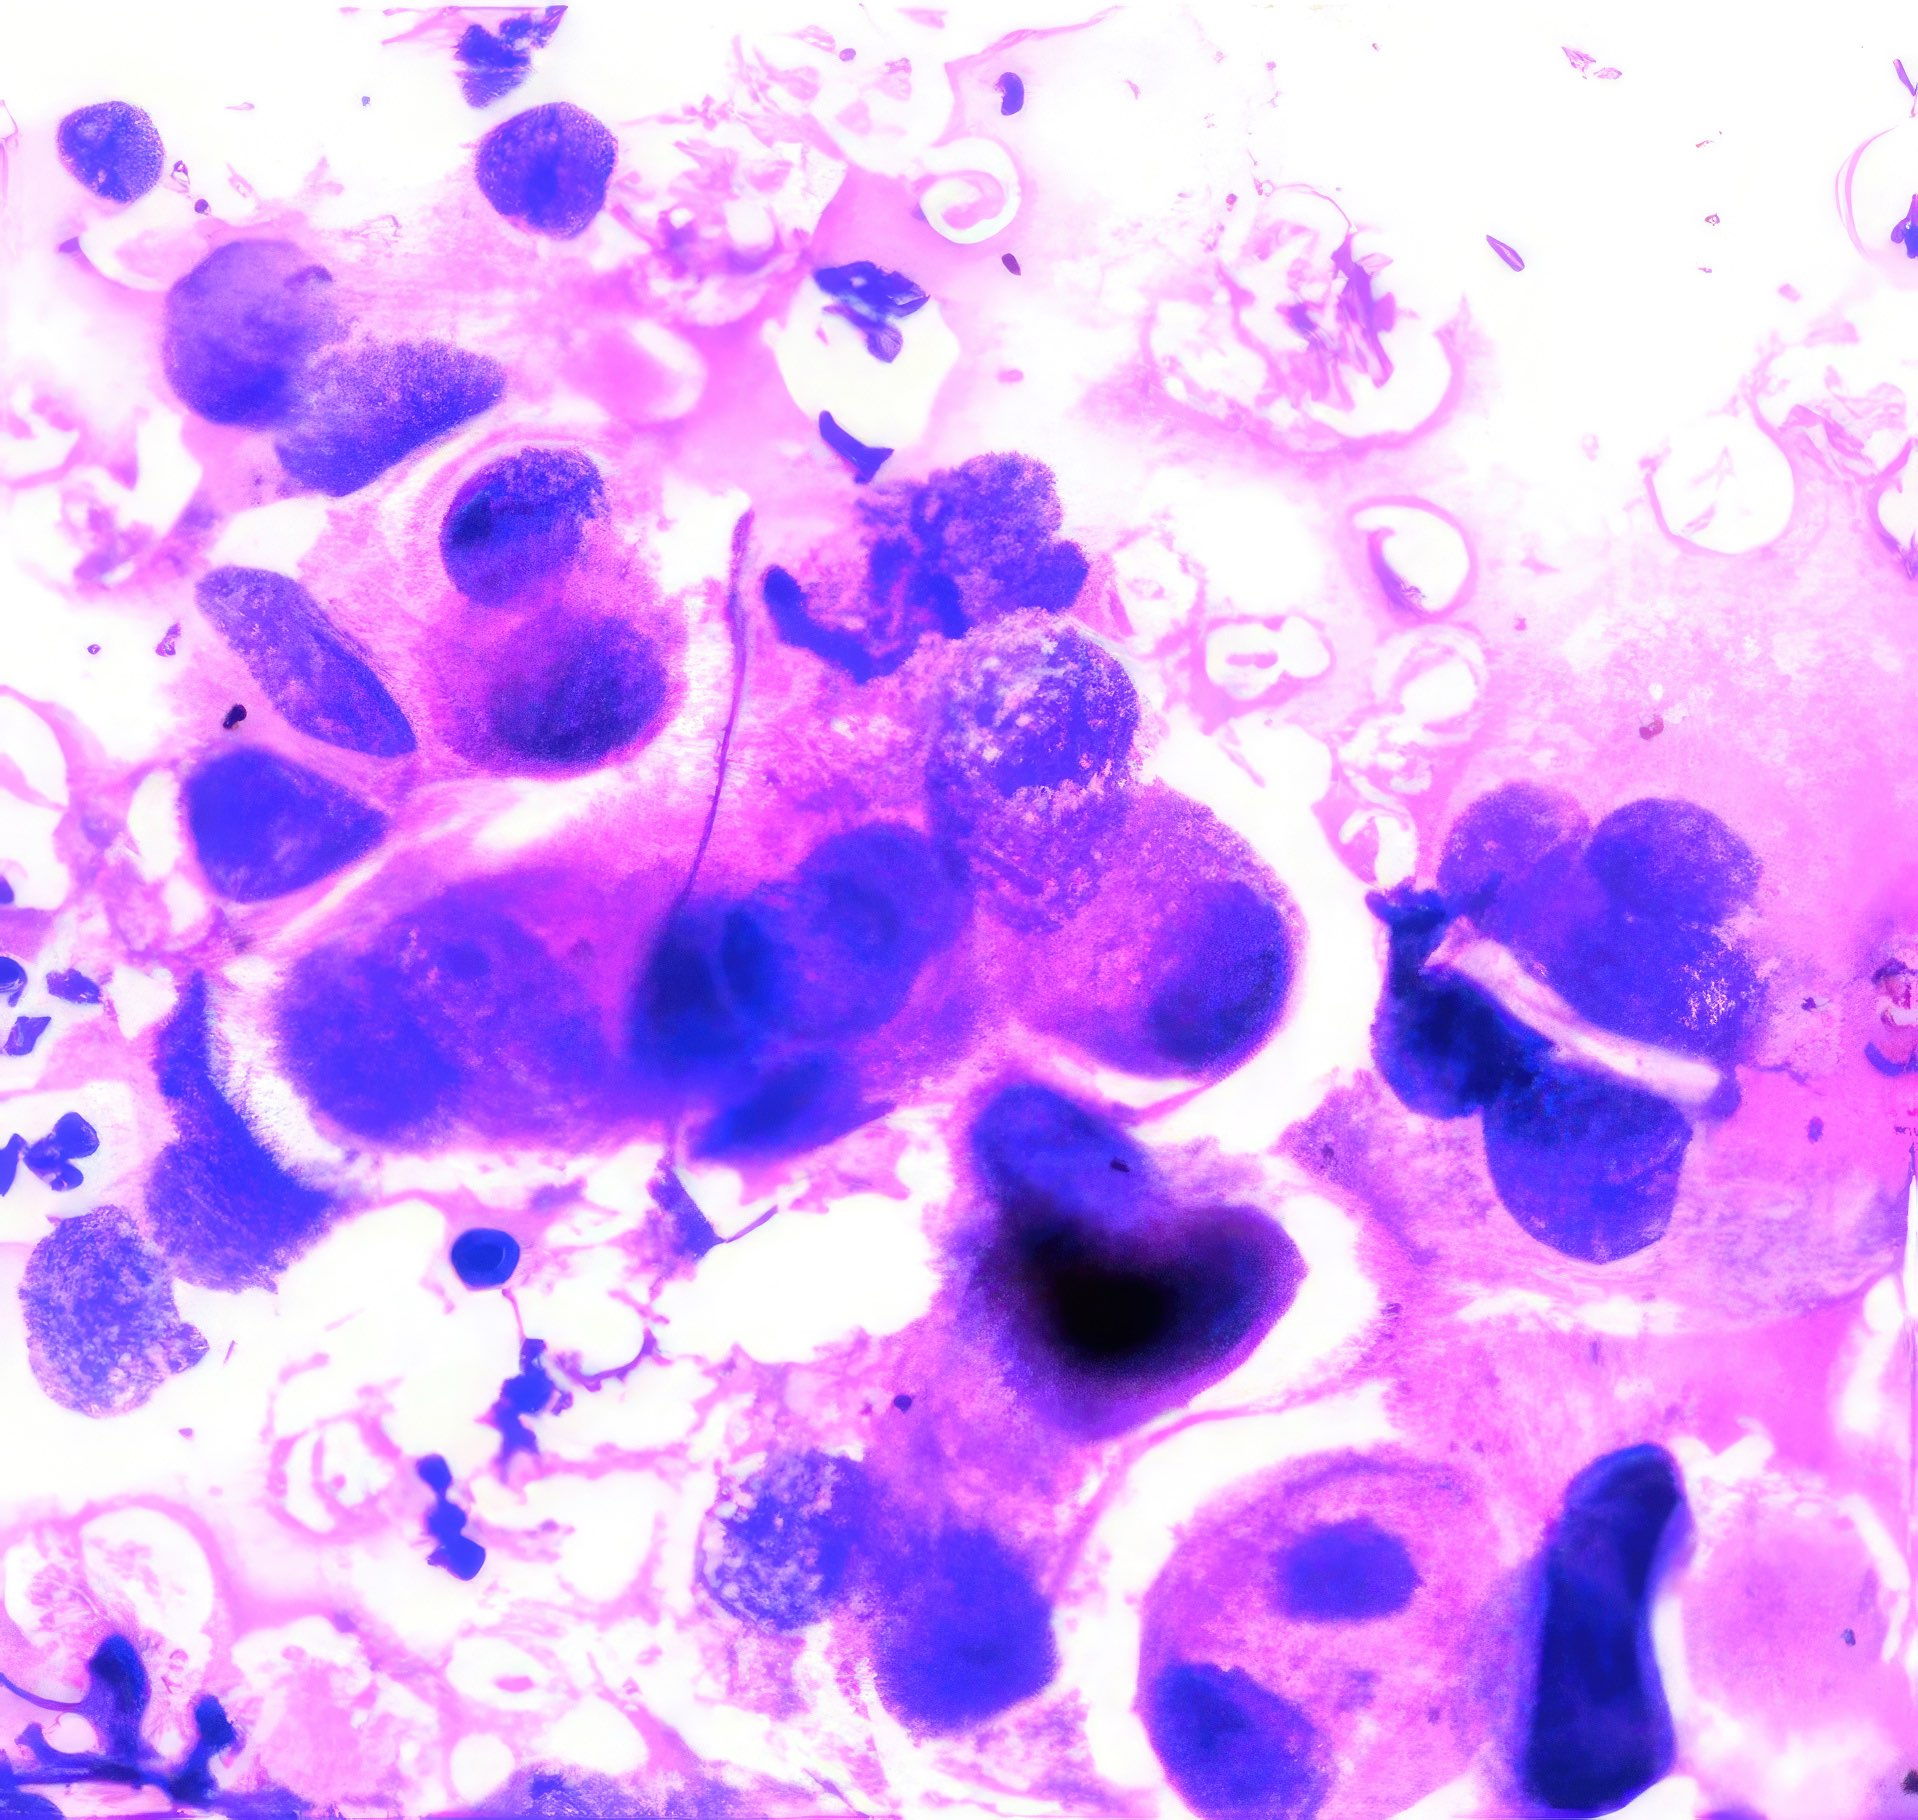

Abbildung 1 – 4: HE-Färbung; 1 – 4, original Obj. 40x, Abb. 4:

zusätzlich vergrößert

Invasive breast carcinoma (IBC NST G3)

Die sich teils überlagernden Zellen erscheinen meist nacktkernig oder haben nur wenig Zytoplasma. Die Kerne variieren deutlich in Form und Größe, sind grob strukturiert und zeigen vereinzelt kleine Chromozentren und Protrusionen. Im Hintergrund etwas Zelldetritus.

Die histologischen Bilder (Abb. 1 und 2) bestätigen die zytologische Diagnose. Weite Teile des Gewebes sind durchsetzt von Tumorzellen, die nur angedeutet Verbände bilden und deutlich polymorphe Kerne aufweisen.

In diesem Fall bestand schon bei der klinischen Untersuchung kein Zweifel an der Karzinomdiagnose wegen eingezogener Brustwarze, oranger Hautfärbung und vergrößertem axillärem Lymphknoten, was klinisch nach WHO-Klassifikation T4bN1 entspricht. Die zytologische Diagnose eines Mammakarzinoms ist nicht immer so einfach. Dies gilt vor allem für das gut differenzierte tubuläre Karzinom, bei dem Größe und Form der Zellen nur schwer von normalen Zellen zu unterscheiden sind 12. Ähnliches gilt für das lobuläre Karzinom, dessen Zellkerne auch nur wenig in Form und Größe variieren; das auffälligste zytologische Merkmal ist die auch im zytologischen Präparat teilweise nachweisbare Indianfile-artige Anordnung 3. Die Trefferquote professionell durchgeführter FNA liegt knapp über 90%. Mag auch die Trefferquote der Dicknadel-Biopsie noch um wenige Prozent höher sein 4, so bietet die FNA besonders in unterversorgten Ländern den Vorteil, dass die Herstellung der Präparate einfacher, billiger und weniger zeitaufwendig ist.